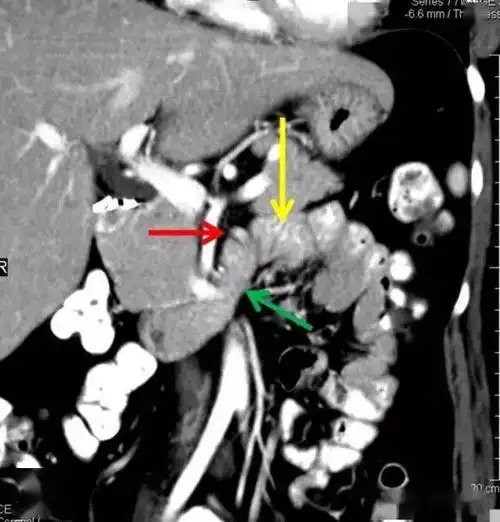

treitz韧带 | 怎么也看不见的屈氏韧带

treitz韧带 | 怎么也看不见的屈氏韧带_解剖